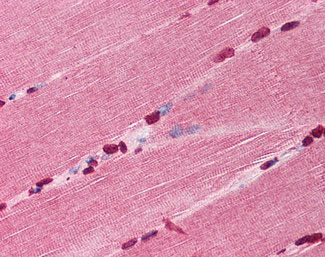

Anti-TIRAP antibody IHC of human skeletal muscle. |